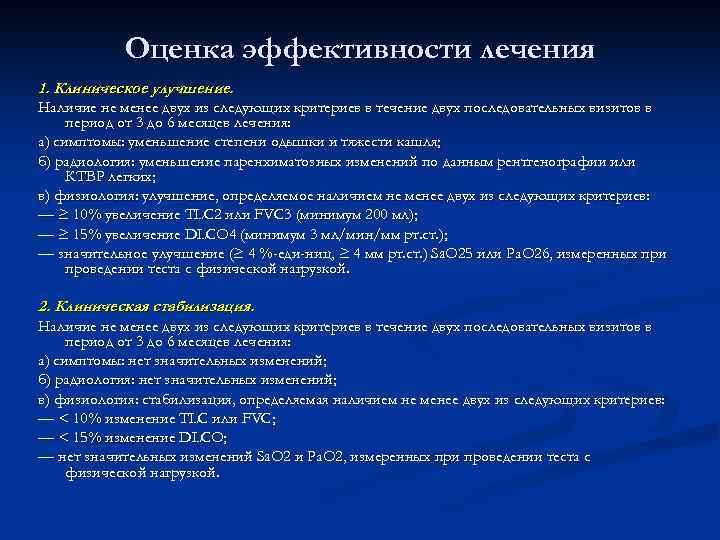

Оценка эффективности лечения 1. Клиническое улучшение. Наличие не менее двух из следующих критериев в течение двух последовательных визитов в период от 3 до 6 месяцев лечения: а) симптомы: уменьшение степени одышки и тяжести кашля; б) радиология: уменьшение паренхиматозных изменений по данным рентгенографии или КТВР легких; в) физиология: улучшение, определяемое наличием не менее двух из следующих критериев: — ≥ 10% увеличение TLC 2 или FVC 3 (минимум 200 мл); — ≥ 15% увеличение DLCO 4 (минимум 3 мл/мин/мм рт. ст. ); — значительное улучшение (≥ 4 %-еди-ниц, ≥ 4 мм рт. ст. ) Sa. О 25 или Ра. О 26, измеренных при проведении теста с физической нагрузкой. 2. Клиническая стабилизация. Наличие не менее двух из следующих критериев в течение двух последовательных визитов в период от 3 до 6 месяцев лечения: а) симптомы: нет значительных изменений; б) радиология: нет значительных изменений; в) физиология: стабилизация, определяемая наличием не менее двух из следующих критериев: — < 10% изменение TLC или FVC; — < 15% изменение DLCO; — нет значительных изменений Sa. О 2 и Ра. О 2, измеренных при проведении теста с физической нагрузкой.

3. Отсутствие эффекта (после 6 месяцев терапии): а) симптомы: увеличение степени одышки и тяжести кашля, не связанное с другими факторами; б) радиология: увеличение паренхиматозных изменений, или признаков сотового легкого, или признаков легочной гипертензии по данным рентгенографии или КТВР легких; в) физиология: ухудшение, определяемое наличием не менее двух из следующих критериев: — ≥ 10% уменьшение TLC или FVC; — ≥ 15% уменьшение DLCO; — значительное ухудшение (≥ 4 %-единиц, ≥ 4 мм рт. ст. ) Sa. О 2 или Ра. О 2, измеренное при проведении теста с нагрузкой. Эффективность лечения больных ИФА прежде всего зависит от сроков начала терапии. Назначение противовоспалительных и цитостатических средств на ранней стадии заболевания повышает эффективность терапии и улучшает прогноз. КТВР — компьютерная томография высокого разрешения TLC — общая емкость легких FVC — форсированная жизненная емкость легких DLCO — диффузионная способность легких по оксиду углерода Sа. О 2 — насыщение артериальной крови кислородом Ра. О 2 — напряжение артериальной крови кислородом